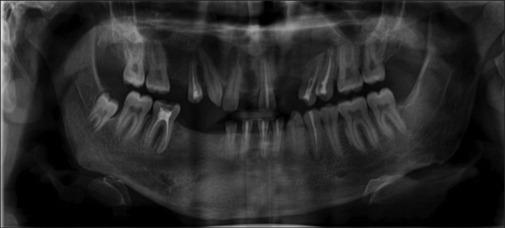

Keratocyst is a developmental odontogenic cyst arising from remnants/rests of the dental lamina with biologic behavior similar to benign neoplasm. The presence of multiple odontogenic keratocysts is rare and seen in Gorlin-Goltz syndrome (GGS). GGS syndrome presents with multisystem involvement and the classical triad of multiple basocellular epitheliomas, keratocysts in the jaws, and bifid ribs; that characterize the diagnosis of this syndrome. Multiple odontogenic keratocyst are the most consistent features of the syndrome in 65%-100% of affected individuals and are generally diagnosed at a very early age. Early diagnosis and proper counseling of the parent and patient might help to reduce the morbidity, encourage follow-up for timely treatment, and help in avoiding ionizing radiation that would lead to the development of malignancies.

牙源性角化囊肿是一种发育性牙源性囊肿,起源于牙板的残余/遗迹,其生物学行为类似于良性肿瘤。多发性牙源性角化囊肿罕见,见于戈林-戈尔茨综合征(GGS)。GGS综合征表现为多系统受累,具有多发性基底细胞上皮瘤、颌骨角化囊肿和肋骨分叉这一经典三联征,这些特征可用于该综合征的诊断。多发性牙源性角化囊肿是该综合征在65%-100%的受累个体中最一致的特征,通常在非常早的年龄被诊断出来。早期诊断并对家长和患者进行适当的咨询可能有助于降低发病率,鼓励进行随访以便及时治疗,并有助于避免导致恶性肿瘤发生的电离辐射。